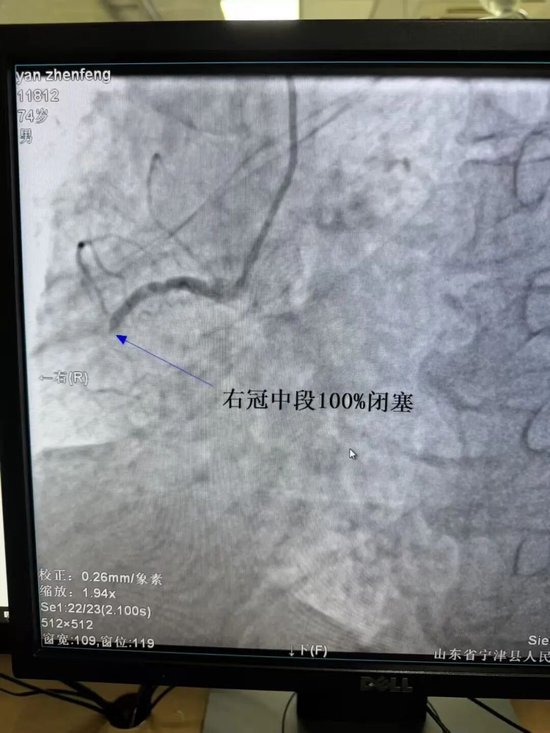

造影结果显示右冠中段狭窄程度达100%,造影时TIMI血流为0级

开通前后对比